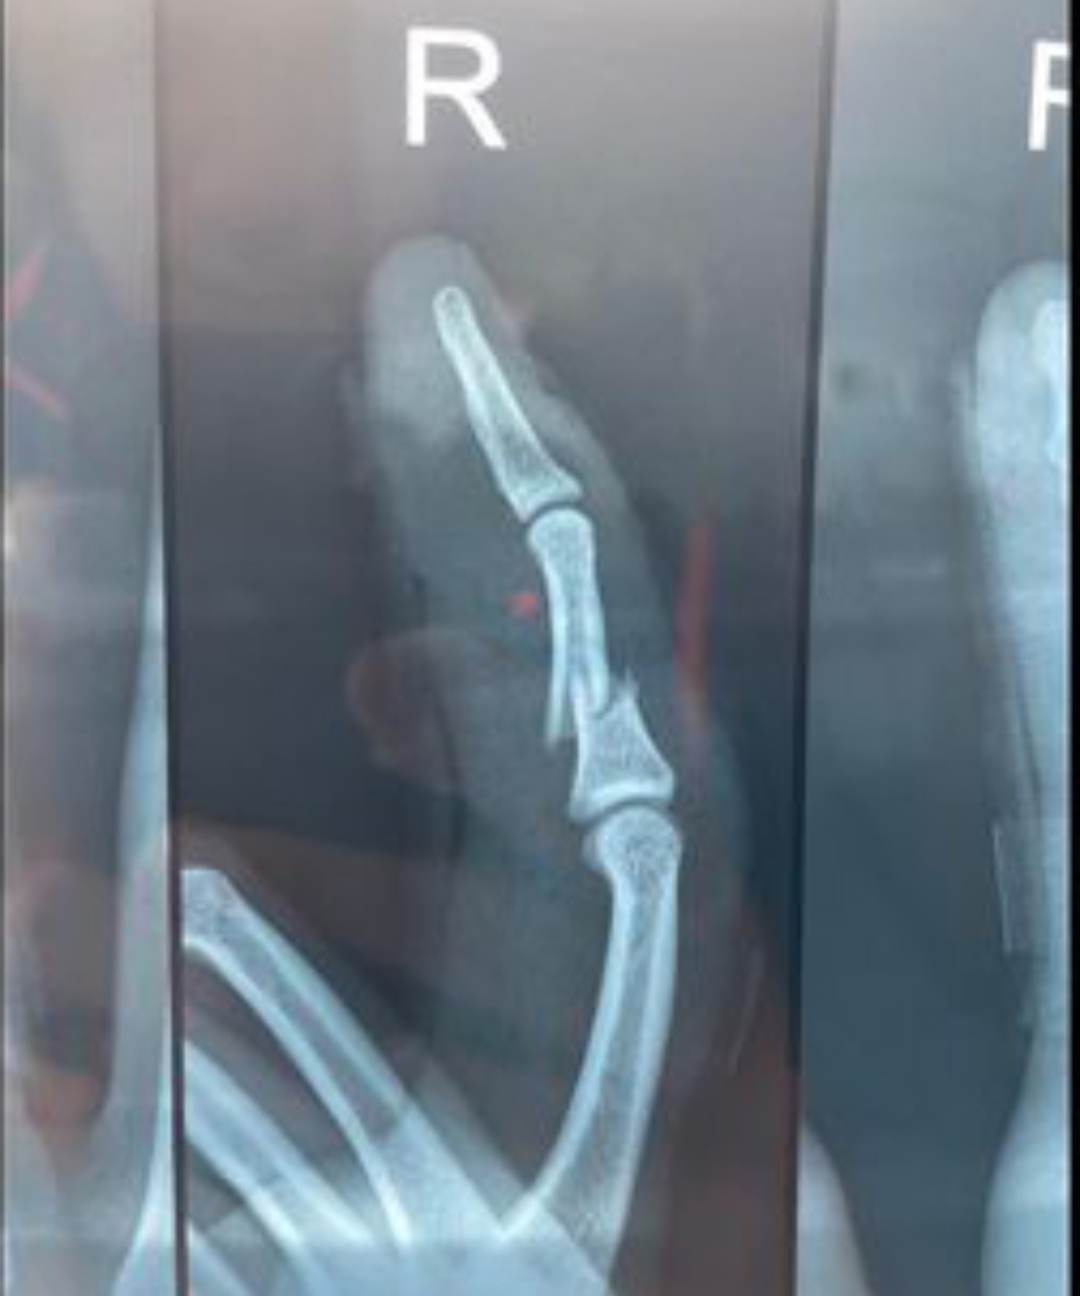

As he gets ready for surgery, Australian all-rounder Cameron Green tweeted a heartbreaking photo of his “broken finger.” While playing in the first inning of the Boxing Day test in Melbourne, Green suffered a finger injury.

The 23-year-old will not play in the third Sydney Test against South Africa as a result of the injury. Following Australia’s victory against South Africa, Green posted images from the match on Instagram. He also uploaded a scan of his fractured finger along with them.